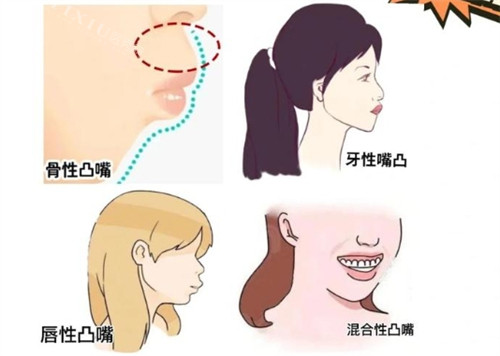

一、什么是骨性嘴凸?

骨性嘴凸主要表现为上颌前突或下颌后缩,导致嘴唇无法自然闭合。与单纯牙齿不齐不同,这种问题涉及颌骨发育异常,需要早期干预才能取得理想结果。